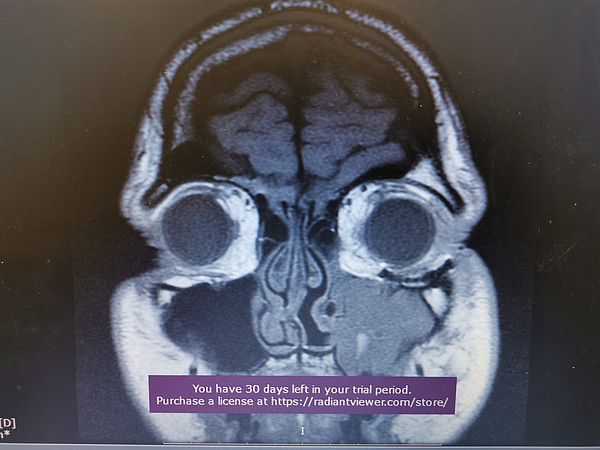

IMG_20211113_071806.